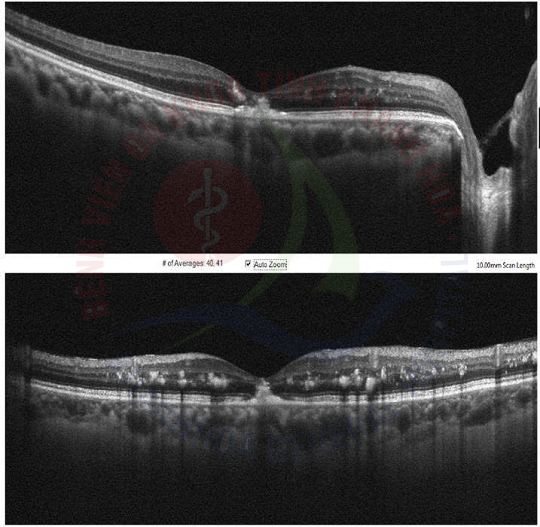

✅ Chụp hình màu đáy mắt và chụp cắt lớp quang học (OCT): Khi có nghi ngờ tổn thương, các phương pháp này giúp đánh giá chi tiết tình trạng phù hoàng điểm và tổn thương võng mạc.

✅ Chụp mạch máu OCT (OCT-A): Đây là một kỹ thuật hiện đại, không xâm lấn, cho phép bác sĩ quan sát chi tiết hệ thống mạch máu ở võng mạc mà người bệnh không cần tiêm thuốc cản quang như phương pháp cũ.